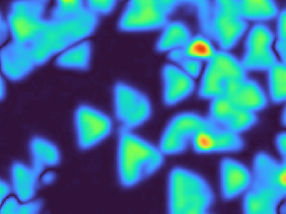

Células muertas (puntos verdes) en una de las zonas neurogénicas (en azul, todas las células) del cerebro de un ratón deficiente en Axl y Mer. En ratones normales no se observa ninguna señal verde. /

CSIC

Los investigadores han “eliminado Axl y Mer” de la microglía de los ratones y han observado que se producía una enorme acumulación de células muertas, solo y exclusivamente en zonas muy concretas del cerebro en las que se generan nuevas neuronas (llamadas zonas de neurogénesis).

La mayoría de las nuevas neuronas generadas durante la neurogénesis mueren durante el proceso de maduración y son reconocidas y eliminadas de form eficiente por la microglía. Por eso, en un “cerebro normal” es muy difícil detectar estas células muertas.